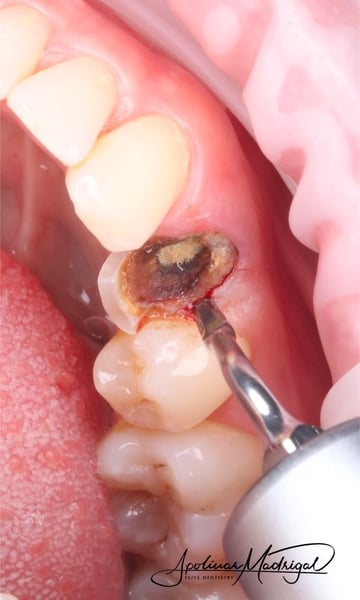

A palatal full thickness flap confirmed our suspicion. The root fragment was removed, the defect was degranulated, and the implant surface was decontaminated with a Nd:Yag laser.